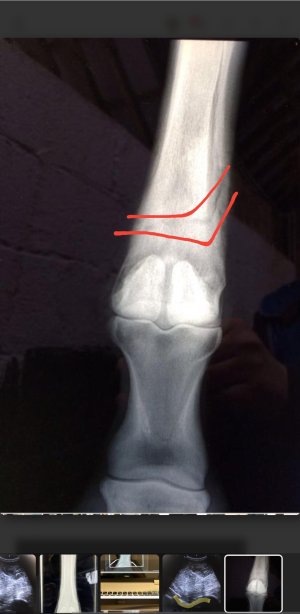

Omg I just realised whatever I just marked goes all the way up the leg 🙈

It does. So this horse started off with a splint bone fracture. At their 4 week xray check up we saw the horizontal crack all the way across the bone too. If that had moved or displaced the horse would be dead. Luckily for the horse we spotted it when we did, wrapped it back up for a few weeks, rehabbed and they raced on for another couple of years. It's a really weird rare one as they rarely crack horizontally without it being fatal. It wasn't seen at he first xray as you don't always see the full extent of the damage for a few days. So it will have been sitting their waiting to show.